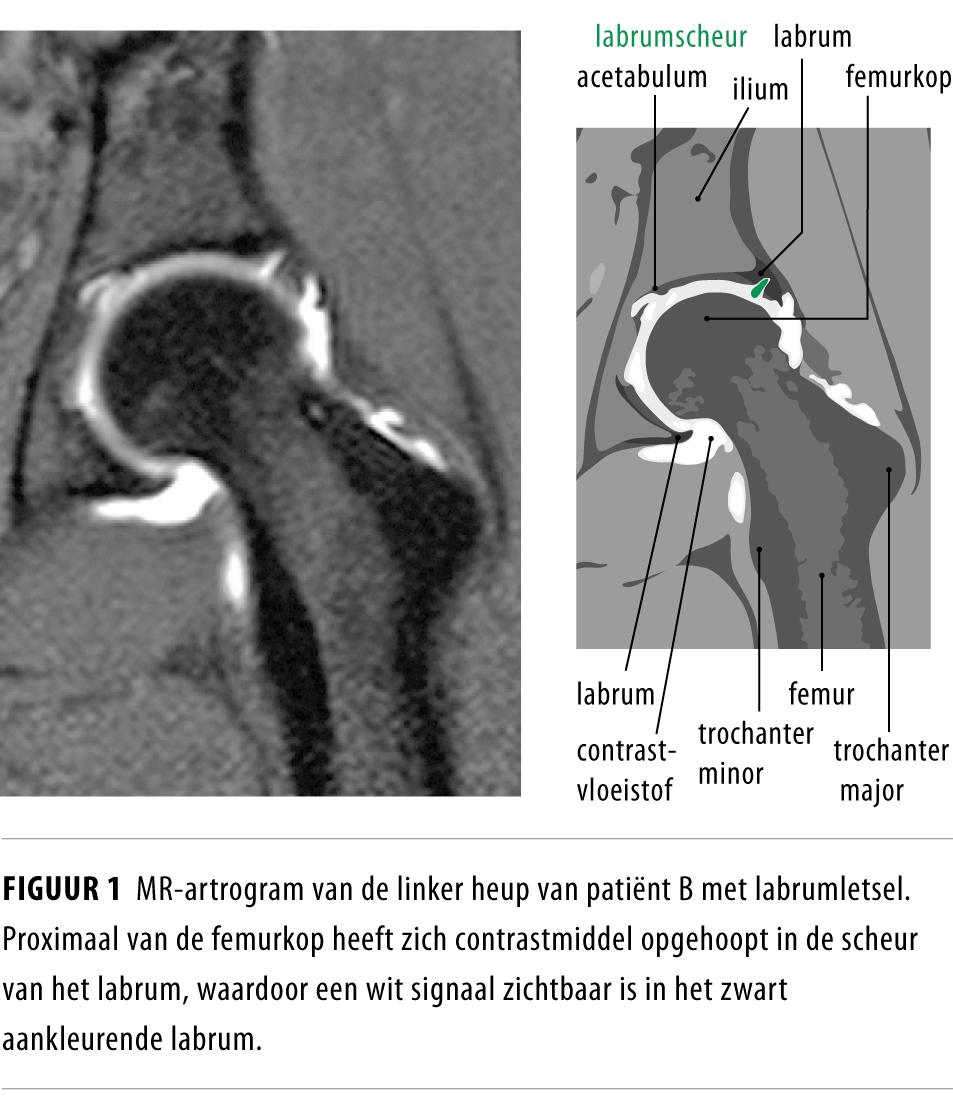

Liespijn bij sporters NTvG